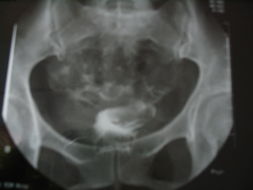

造影不是注入生理盐水,而是经管子注入含碘造影剂,用X线观察,摄片。系列的片子能够动态显示造影剂充盈宫腔,通过卵管,并且在盆腔中弥散的情况。